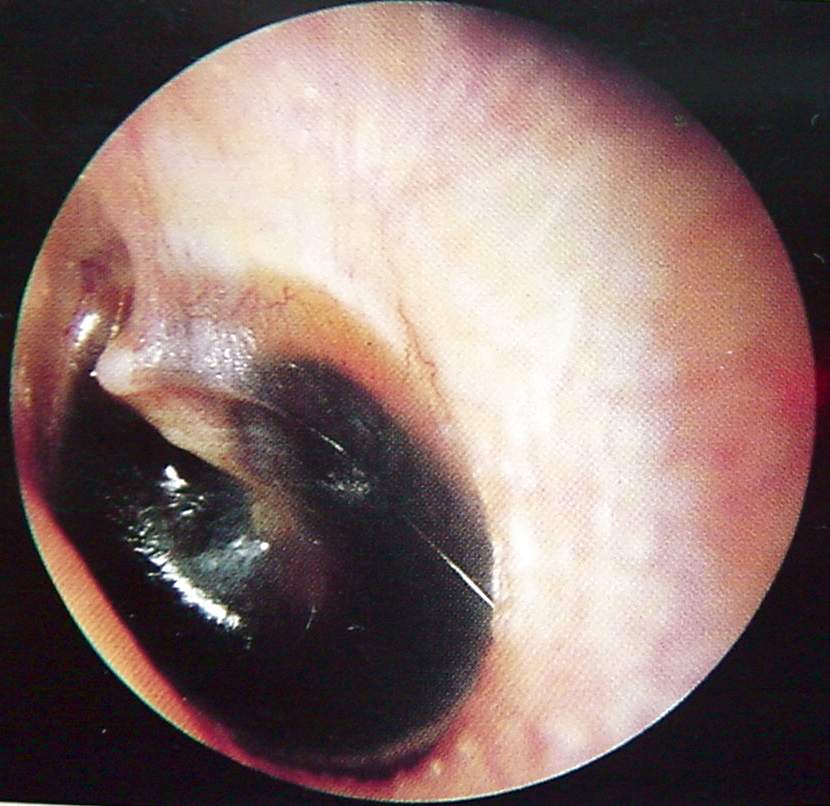

Ear Clinical Photos for Static Stations